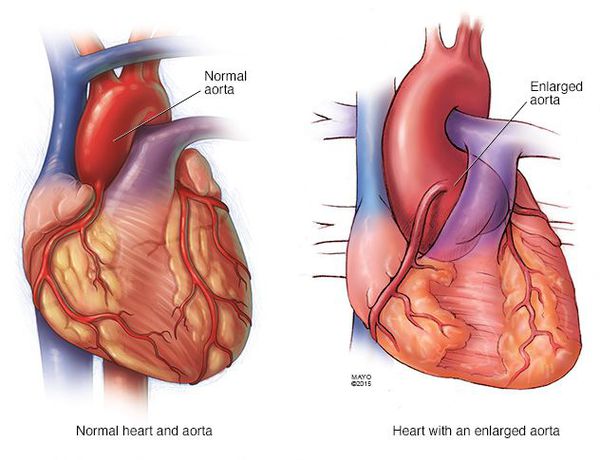

Sindrom marfana tema nauchnoj stati po klinicheskoj medicine chitajte besplatno tekst nauchno issledovatelskoj raboty v elektronnoj biblioteke kiberleninka (Тип файлу jpg)

Sindrom Marfana Tema Nauchnoj Stati Po Klinicheskoj Medicine Chitajte Besplatno Tekst Nauchno Issledovatelskoj Raboty V Elektronnoj Biblioteke Kiberleninka

Sindrom marfana tema nauchnoj stati po klinicheskoj medicine chitajte besplatno tekst nauchno issledovatelskoj raboty v elektronnoj biblioteke kiberleninka (Тип файлу jpg)

Sindrom Marfana Tema Nauchnoj Stati Po Klinicheskoj Medicine Chitajte Besplatno Tekst Nauchno Issledovatelskoj Raboty V Elektronnoj Biblioteke Kiberleninka